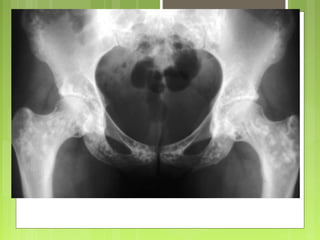

A nivel de la cadera: las localizaciones más frecuentes son próximas a los

cartílagos de crecimiento

A nivel dela cadera: las localizaciones más frecuentes son próximas a los cartílagos de crecimiento Radiografía simple  Signos de benignidad :  imagen bien definida  cortical normal